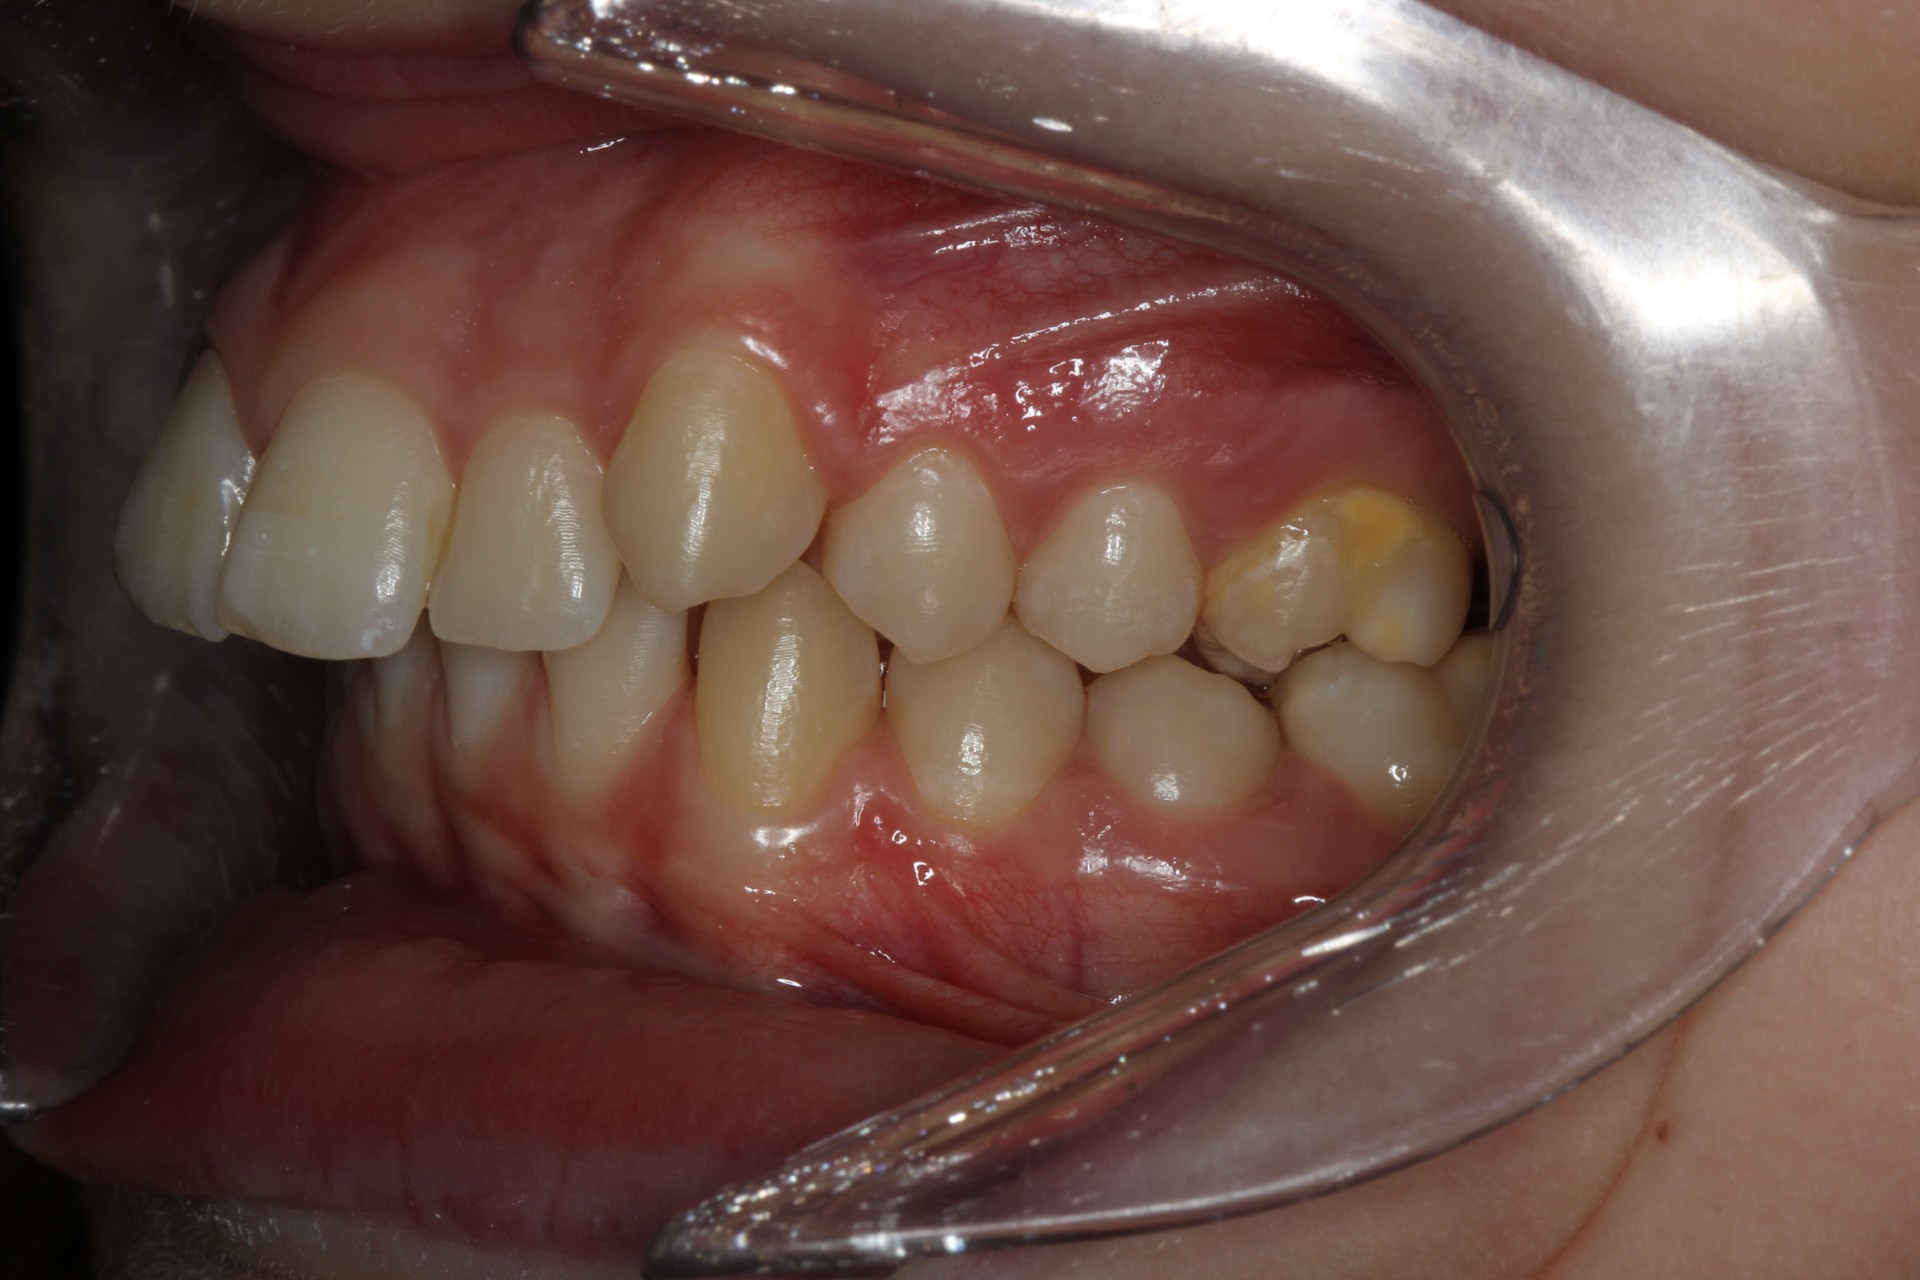

Protruding front teeth – Child case